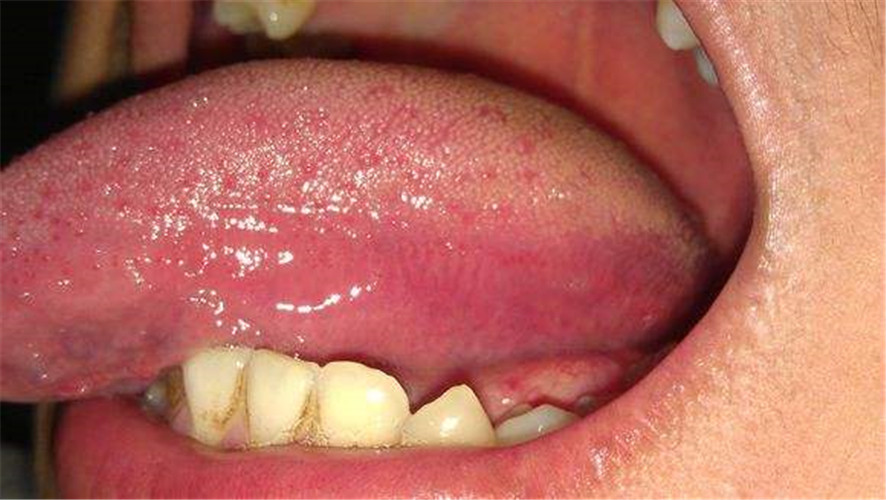

舌頭白色念珠菌感染